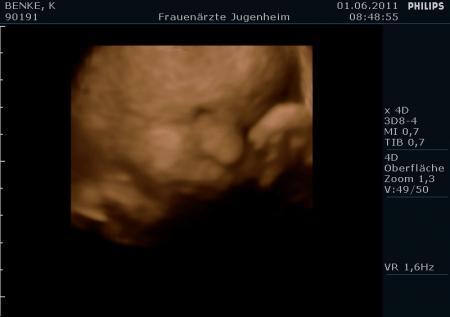

mein baby in der 30. ssw

wie süüüüssss er ist, ich bin jetzt schon total verliebt:) an alle schonmamis: sahen eure zwerge den 3d bildern ähnlich?

Bild zu mein baby in der 30. ssw - Forum für August - Mamis